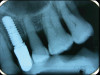

Fig 13. Radiograph depicting crestal bone loss around mandibular implants.

The first step in preventive strategies must be to perform a correct diagnosis of the peri-implant condition by accurately assessing the health of the peri-implant hard and soft tissues through periodontal probing and periapical radiographs at the time of definitive prosthetic installation. These measurements should be considered the baseline diagnosis and, therefore, represent a true starting point for evaluating the changes on the radiographic bone levels and probing pocket depths (PPD) at future recall appointments (Figure 1 and Figure 2).6 Although probing depth measurements of peri-implant tissues do not have the same diagnostic value as probing periodontal tissues, there is evidence that BOP is the most objective sign of peri-implant tissue inflammation; significant deepening of PPD compared with baseline measurements is also a sign of disease that indicates the need to perform a radiographic evaluation (Figure 3 through Figure 5).6,10,11

Following a similar paradigm of treating peri-implantitis the same way that periodontitis is regularly successfully treated, based on the mechanical removal of biofilms adhered to implant/abutment surfaces, different protocols of nonsurgical implant debridement using different mechanical, physical, and chemical mechanisms have been evaluated (Figure 12 through Figure 15). In general, the use of different protocols combining treatments aimed to decontaminate the implant surface (eg, mechanical, lasers) and control the infection process (eg, antiseptics, antibiotics) have shown clinical and significant improvements in the commonly used surrogate outcomes (mean reductions in PPD of around 1.2 mm and mean reductions in the scores of BOP of about 50%) but have not resulted in disease resolution18 or a high degree of predictablility.19 There is currently no specific nonsurgical therapy that has shown efficacy in the resolution of peri-implantitis, and the clinical improvements reported in the clinical studies were not sufficient for the arrest of the disease, leaving the standard of care in the treatment of peri-implantitis as surgical in most cases.20